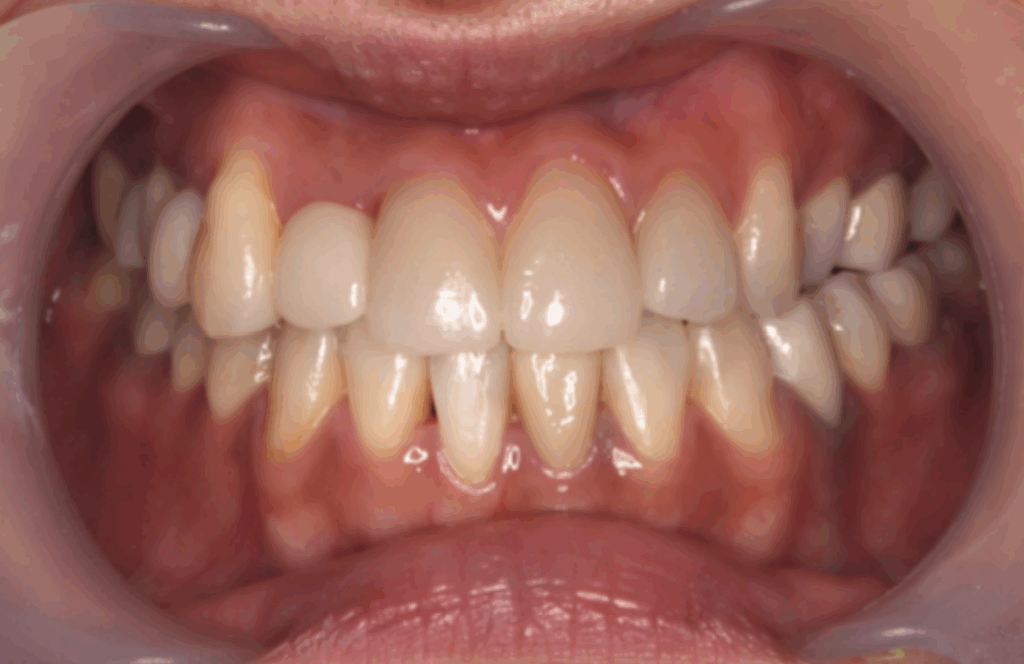

■ デンタルチームジャパンの矯正治療の特徴

デンタルチームジャパンでは、

お子様・女性・ご年配の方まで幅広い患者様に矯正治療を行っており、

豊富な症例実績があります。

▼ 取り扱い矯正装置

① 従来のワイヤー矯正(メタルブラケット)

効率が高く、幅広い症例に対応可能。